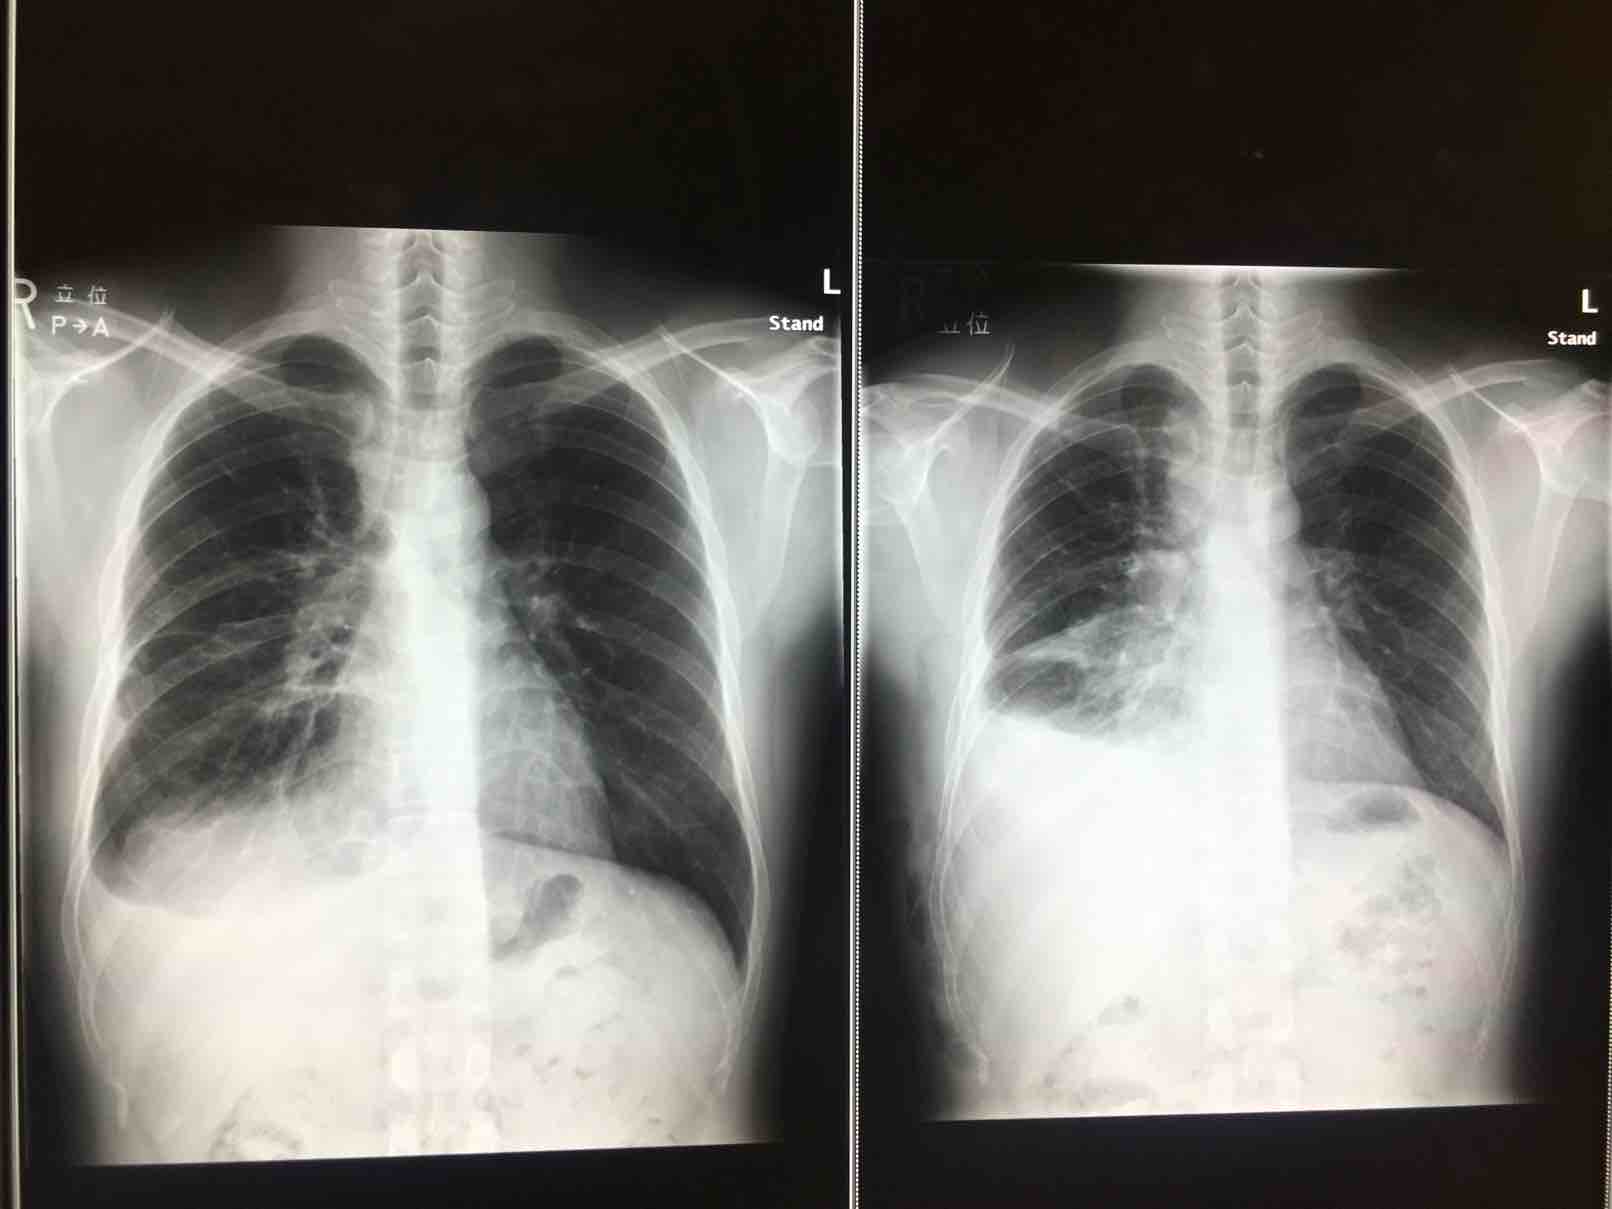

肺癌 腺癌 4期 胸膜扩散 淋巴扩散 ALK阳性

我是2016年7月确诊的肺癌腺癌ALK变异,那时候已经右肺积水200cc,淋巴转移,咳嗽非常厉害,痰非常多。我的主治医,直接推荐的ALECENSA,我吃了一年了,出了一开始的味觉异常意外没有其他副作用。现在一个月跑步跑120公里,几乎痊愈

陈波医生日文的立位与中文是一样的,但为何你的胸片看不到其他信息,比如姓名。你这片的格式跟国内的太吻合了,而且反复强调有42天剩药,这点有质疑,如果是半量吃,你说的剩余的药后面也要继续用啊,强调有剩,这个逻辑其实不严格。你也是想学陈医生走搞笑路线吗

陈波医生提供了日本药店这个渠道,我顺便想问一下,你左边当时那么多胸水,左胸会痛吗